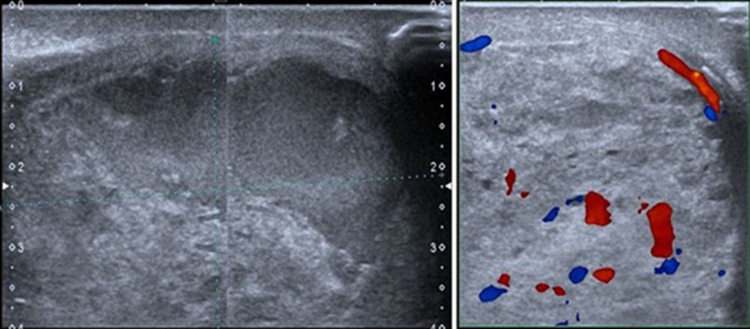

Case presentation: A 20-year-old adult male presented with a painful and palpable mass in his right testicle. The patient had orchidopexy at six months old but had been asymptomatic until his recent hospital visit. There was no previous history of cancer. Tumor markers including AFP and β-HCG were found to be elevated. Preoperative ultrasonograghy (USG) showed a solid and cystic mass of the right testis with increased vascularization. Following these findings, the patient underwent an orchidectomy. Histopathology examination revealed mixed type NSGCT of embryonal and choriocarcinoma. However, after completing four cycles of chemotherapy, a CT scan evaluation showed an enlarged mass in the abdomen, which was confirmed to be a mature teratoma.